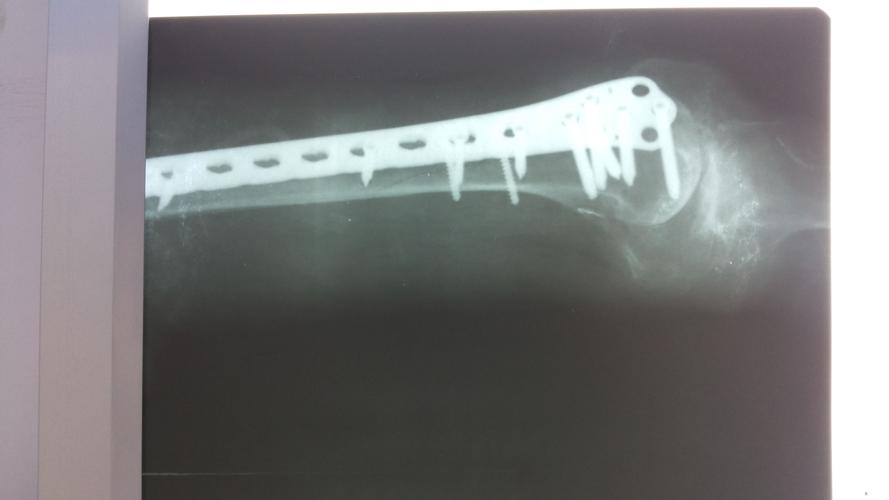

信号灯之二:胫骨下段1/3螺旋形骨折